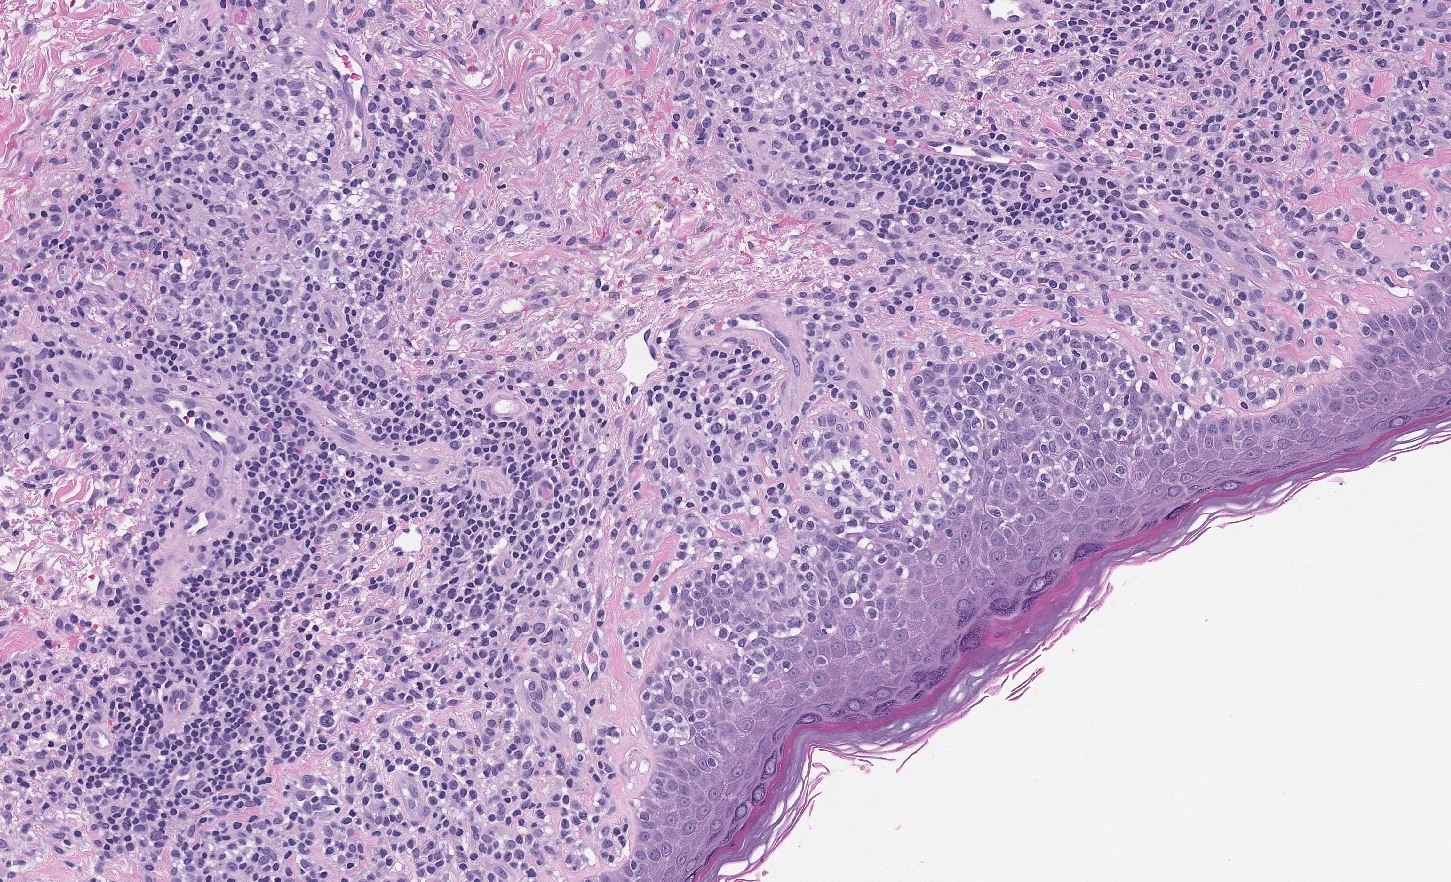

Case: Skin